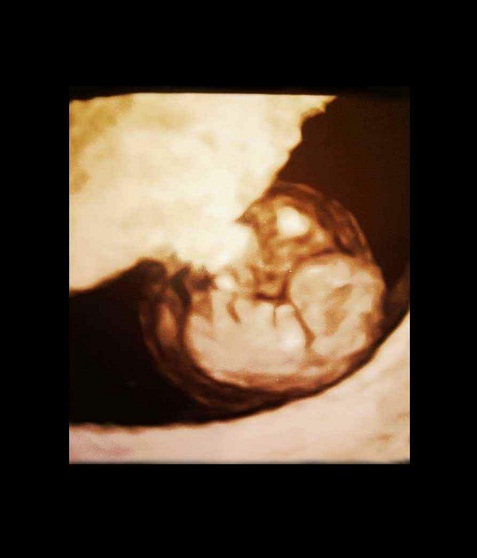

三维图

第8周的胚胎大约有16毫米长,看上去像颗葡萄。胚胎的器官已经开始有明显的特征,手指和脚趾间看上去有少量的蹼状物。这时胚胎像跳动的豆子一样开始有运动。因为骨髓还没有成形,现在由肝脏来生产大量的红细胞,直到骨髓成形后去接管肝脏的作用。

胚胎的器官特征开始明显,各个不同的器官开始忙碌地发育。从现在开始到20周,你的胎儿将迅速成长,并且在几个星期内就会有明显的轮廓,这个时期的成长速度就像孕早期心脏和大脑的发育时期一样。现在各种复杂的器官都开始成长,牙和腭开始发育,耳朵也在继续成形,胎儿的皮肤像纸一样薄,血管清晰可见。